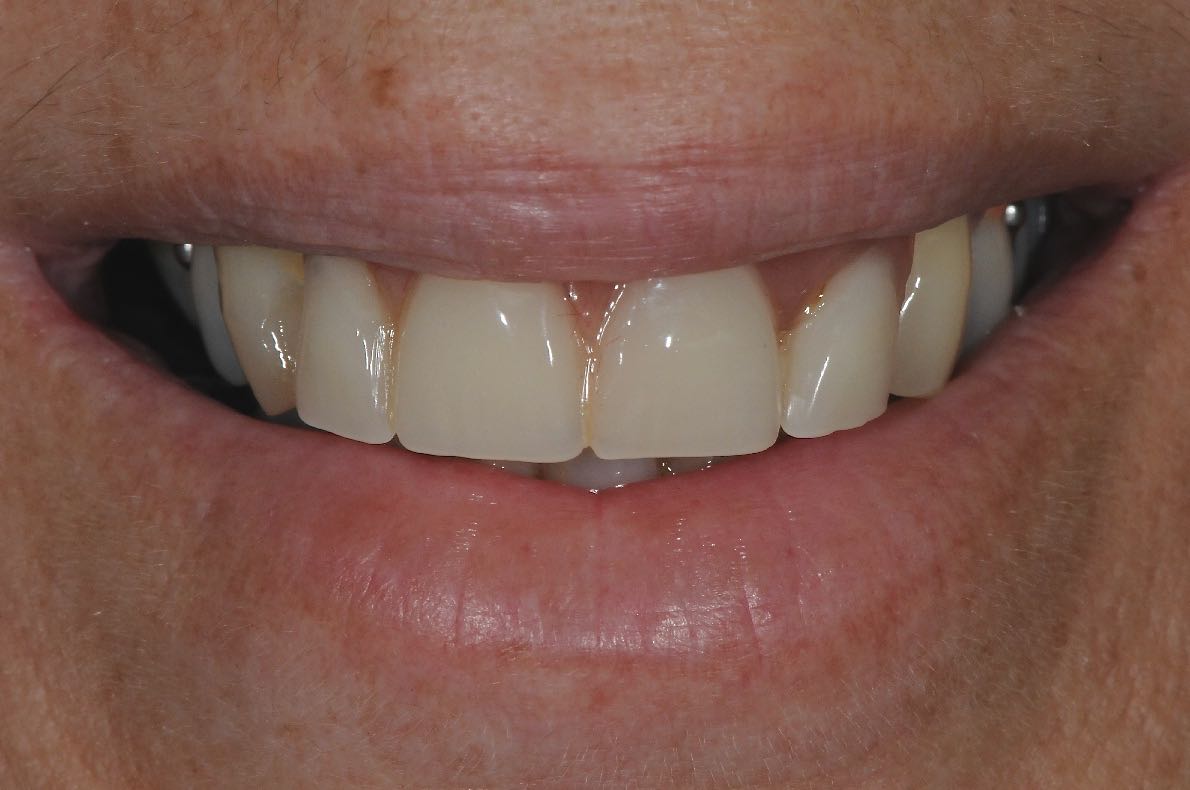

Two implants were placed and then a 4-tooth bridge was made and fitted to the implants. The bridge was secure, functional, and not as bulky as the denture.

The lady was delighted with her treatment. Her new bridge looked and felt almost the same as natural teeth, and she no longer had to worry again about it falling out at an inopportune time !